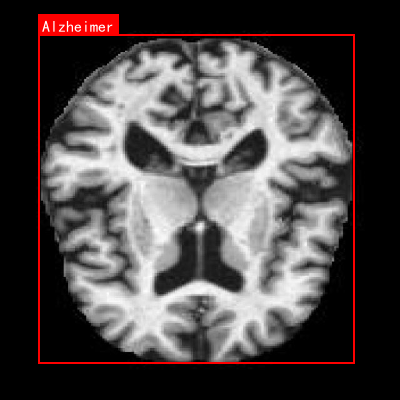

图1:不同神经退行性疾病的MRI影像特征对比,从左到右分别为健康对照组、阿尔茨海默病和帕金森病患者

本数据集名为Enfermedades_cerebro,版本为v1,创建于2024年6月14日,是一个专注于神经退行性疾病诊断的医学影像数据集。该数据集通过qunshankj平台构建,采用CC BY 4.0许可协议进行授权,共包含999张脑部横断面磁共振成像(MRI)图像,所有图像均以YOLOv8格式进行了标注。数据集涵盖了三个主要类别:阿尔茨海默病(Alzheimer)、健康对照组(CONTROL)以及帕金森病(parkinson),为神经退行性疾病的计算机辅助诊断提供了宝贵的训练资源。在预处理阶段,所有图像均经过了自动方向校正(EXIF方向信息被剥离)并统一调整为640×640像素尺寸,但未应用任何图像增强技术。数据集按照标准划分方式组织为训练集、验证集和测试集三个子集,为模型开发与评估提供了完整的数据支持。从影像学特征来看,数据集中的MRI图像清晰展示了大脑的解剖结构,包括灰质与白质的对比、脑沟回形态、侧脑室大小等关键指标,这些特征对于区分不同类型的神经退行性疾病具有重要价值。特别是阿尔茨海默病的图像,呈现出典型的脑萎缩表现,如侧脑室扩大、脑沟增宽、脑回变薄等病理特征,为算法学习提供了直观的视觉依据。该数据集的开发与应用,有望提高神经退行性疾病的早期诊断准确性,辅助临床医生进行更高效的疾病筛查与评估。